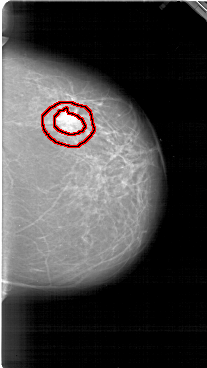

FILE: A_1950_1.RIGHT_MLO.OVERLAY

TOTAL_ABNORMALITIES 1

ABNORMALITY 1

LESION_TYPE MASS SHAPE IRREGULAR MARGINS SPICULATED

ASSESSMENT 5

SUBTLETY 5

PATHOLOGY BENIGN

TOTAL_OUTLINES 1

BOUNDARY

RIGHT_MLO LINES 6391 PIXELS_PER_LINE 3826 BITS_PER_PIXEL 12 RESOLUTION 43.5 OVERLAY